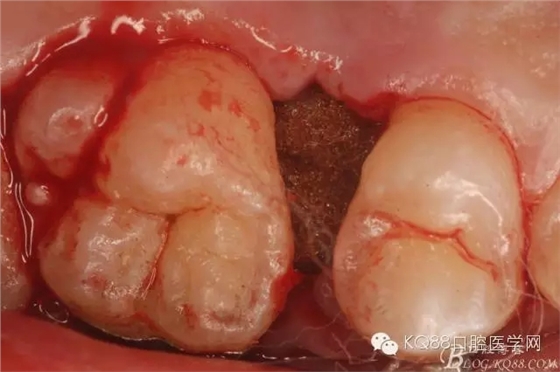

圖21.相鄰牙齒毫發(fā)無(wú)損,牙槽窩形態(tài)正常,無(wú)破壞。